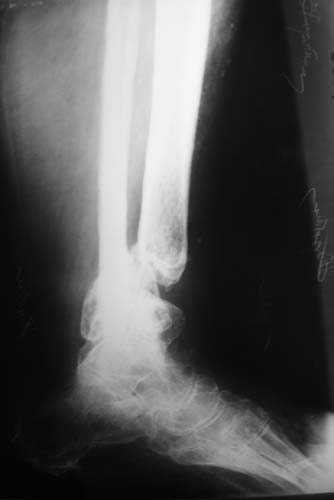

Женщина, 62 года. Травма 2 года назад в результате ДТП. Находится на лечении с 30.10.06 года с диагнозом: Несросшийся перелом дистальной трети правой большеберцовой кости с угловыми деформациями дистального отдела конечности, дефектом костной ткани.

Рубцовой деформацией мягких тканей медиальной поверхности дистальной трети голени. Нейротрофические нарушения. Посттравматический остеопороз. Дегенеративно-дистрофический остеоартроз правого голеностопного сустава.Сопутствующая патология.: ЖКБ, хронический калькулезный холецистит в стадии ремиссии. МКБ, хронический пиелонефрит в стадии ремиссии.Ожирение 3 ст. Посттромбофлебитический синдром нижних конечностей, ХВН 2 ст. Посттравматическая нейропатия левого малоберцового нерва с парезом левой стопы. Какие предложения по тактике лечения? Заранее благодарю!

Голеностопный сустав тут, видимо, потерян. Так что надо думать только про стабилизацию. Какие из существующих вариантов артродеза доступны, и какой из доступных оптимален? Антон, есть ли смысл обсуждать варианты с закрытым штифтованием, доступно оно? Если да, то Алексей Семенистый предлагает вполне жизнеспособный план (хотя можно и антгерадно сделать). Если нет, то надо что-то придумывать с аппаратом. Наверно, латеральным доступом кпереди от fibula с ее пересечением открыться, и что-то костно-пластическое делать.